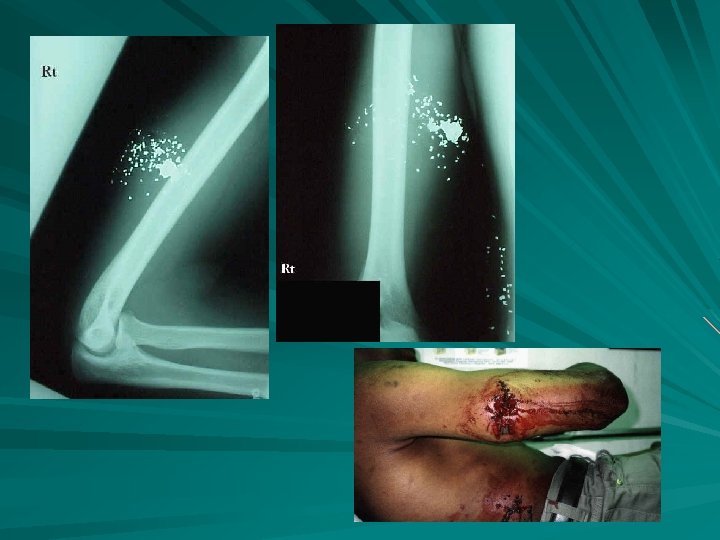

Fractured Forearm

FX RADIAL HEAD

greenstick

comminuted Open fracture